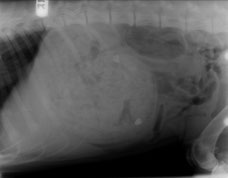

レントゲンでは胃に食塊と思われるものが写り、触診でも胃が硬い感じでした。

2日後に嘔吐はないが食欲低下は継続していて、レントゲンの映像が変化ないので開腹しました。